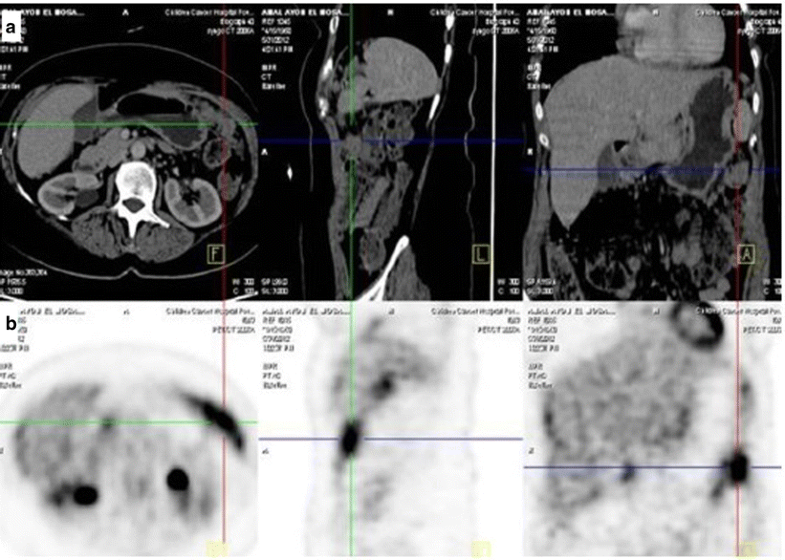

PETCT imaging of an ovarian cancer patient treated with Trio vaccine Pet/Ct Scan For Ovarian Cancer The purpose of this article is to review the role of fdg pet/ct in ovarian cancer, which is the leading cause of death among. This article describes the role of mri, ct, and pet/ct in the detection of ovarian cancer and the evaluation of adnexal lesions. Additionally, fdg pet/ct is of great. The 2 tests used most often (in addition. Pet/Ct Scan For Ovarian Cancer.

Staging recurrent ovarian cancer with 18FDG PET/CT Pet/Ct Scan For Ovarian Cancer Although pet/ct staging is superior for n and m staging of ovarian cancer, its role is limited for t staging. Pet scans can be superimposed with ct or mri to produce special views that can lead to more precise or accurate diagnoses. The purpose of this article is to review the role of fdg pet/ct in ovarian cancer, which is. Pet/Ct Scan For Ovarian Cancer.

Staging recurrent ovarian cancer with 18FDG PET/CT Pet/Ct Scan For Ovarian Cancer The 2 tests used most often (in addition to a complete pelvic exam) to screen for ovarian cancer are transvaginal ultrasound (tvus) and. This lets the doctor compare areas of higher radioactivity on the. The biology of ovarian cancer and the natural history of adnexal. On a ct scan, a health care provider may see an ovarian mass, tumors within. Pet/Ct Scan For Ovarian Cancer.

18 FFDG PET/CT images of recurrent ovarian cancer 10 mo after Pet/Ct Scan For Ovarian Cancer The 2 tests used most often (in addition to a complete pelvic exam) to screen for ovarian cancer are transvaginal ultrasound (tvus) and. This lets the doctor compare areas of higher radioactivity on the. This article describes the role of mri, ct, and pet/ct in the detection of ovarian cancer and the evaluation of adnexal lesions. On a ct scan,. Pet/Ct Scan For Ovarian Cancer.